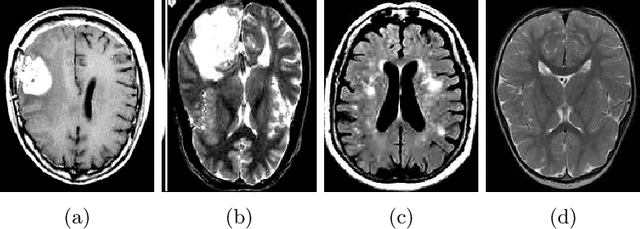

Abstract:This paper presents a research study on the use of Convolutional Neural Network (CNN), ResNet50, InceptionV3, EfficientNetB0 and NASNetMobile models to efficiently detect brain tumors in order to reduce the time required for manual review of the report and create an automated system for classifying brain tumors. An automated pipeline is proposed, which encompasses five models: CNN, ResNet50, InceptionV3, EfficientNetB0 and NASNetMobile. The performance of the proposed architecture is evaluated on a balanced dataset and found to yield an accuracy of 99.33% for fine-tuned InceptionV3 model. Furthermore, Explainable AI approaches are incorporated to visualize the model's latent behavior in order to understand its black box behavior. To further optimize the training process, a cost-sensitive neural network approach has been proposed in order to work with imbalanced datasets which has achieved almost 4% more accuracy than the conventional models used in our experiments. The cost-sensitive InceptionV3 (CS-InceptionV3) and CNN (CS-CNN) show a promising accuracy of 92.31% and a recall value of 1.00 respectively on an imbalanced dataset. The proposed models have shown great potential in improving tumor detection accuracy and must be further developed for application in practical solutions. We have provided the datasets and made our implementations publicly available at - https://github.com/shahariar-shibli/Explainable-Cost-Sensitive-Deep-Neural-Networks-for-Brain-Tumor-Detection-from-Brain-MRI-Images